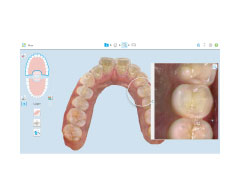

特殊なカメラを使って口腔内をスキャンして様々な角度から撮影し、3D画像データを採取します。当院では歯型採取を迅速かつ快適に行うために、口腔内スキャナーを2台導入しています。1台はマウスピース矯正(インビザライン)に、もう1台は詰め物や被せ物の治療に使用します。

非常に高い精度を持ち、撮影時間も短いため、従来の印象材を使った歯型採取に比べて患者さんの負担が大幅に軽減されます。またインビザラインと連携できるiTeroを使うことで、治療前後のシミュレーションも可能です。